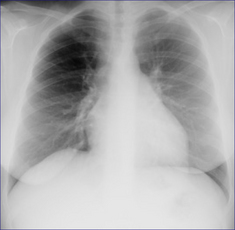

image

Figure 23.3 Westermark sign? Be very careful. Middle-aged female. Intermediate clinical probability of a pulmonary embolus. The right lung is hypertransradiant (blacker) compared with the left lung. Two technical factors are contributing to this:(1) lateral decentering of the x-ray beam;(2) asymmetric compression of the chest wall soft tissues on the right side. The VQ scan was entirely normal.